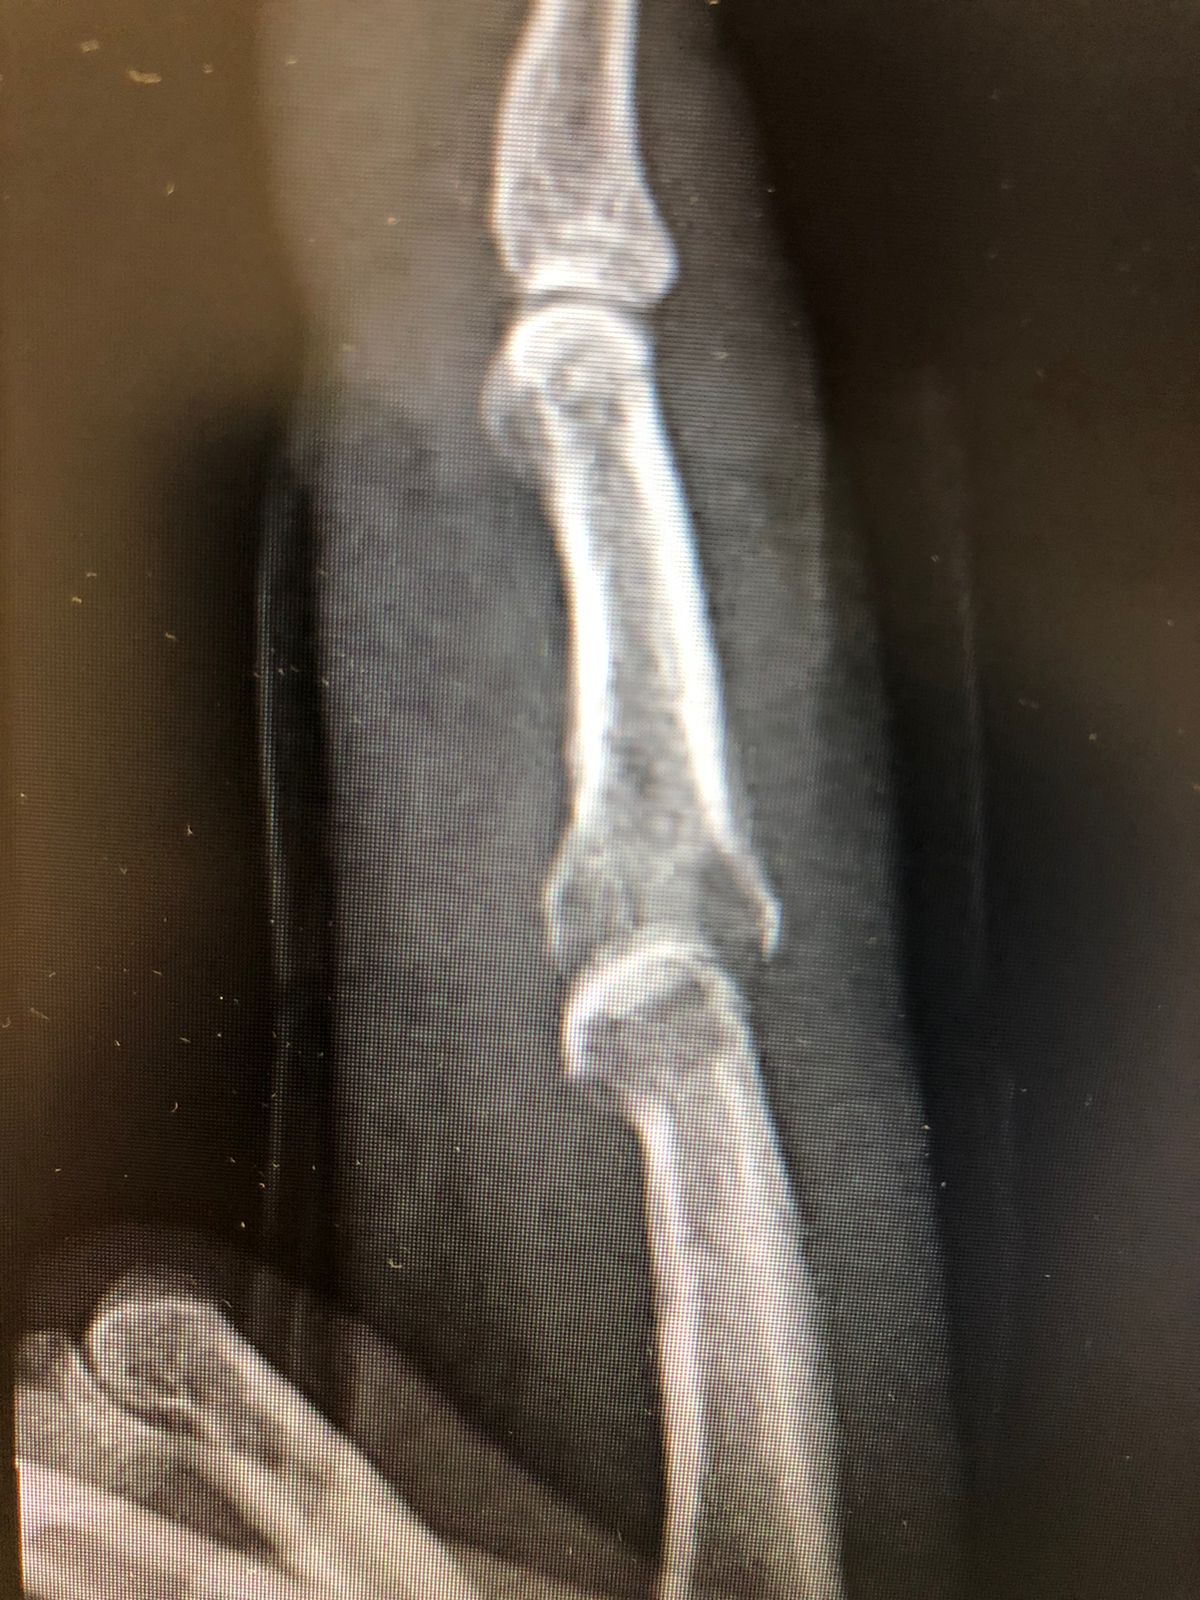

🧪 Diagnóstico

• Radiografia (alterações tardias)

osteomielite por mordedura